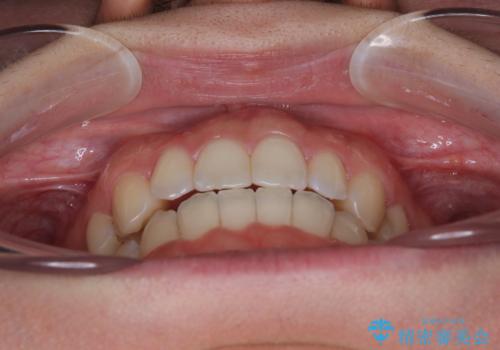

【モニター】オープンバイトをインビザライン矯正で治す

- 前歯の開咬を気にして来院された患者様です。

開咬の治療は、前歯を閉じるように動かすとともに、上下臼歯を圧下(骨内にめり込ませる)させることで進めて行きます。

インビザラインは臼歯の圧下を効果的に行えるため、インビザラインを用いて矯正治療を行うこととしました。

オープンバイトは舌の突出癖により誘発され、治療後も突出癖が残っている容易に後戻りしてしまいます。

治療期間を短縮するためにも、舌突出癖の改善が極めて重要となります。